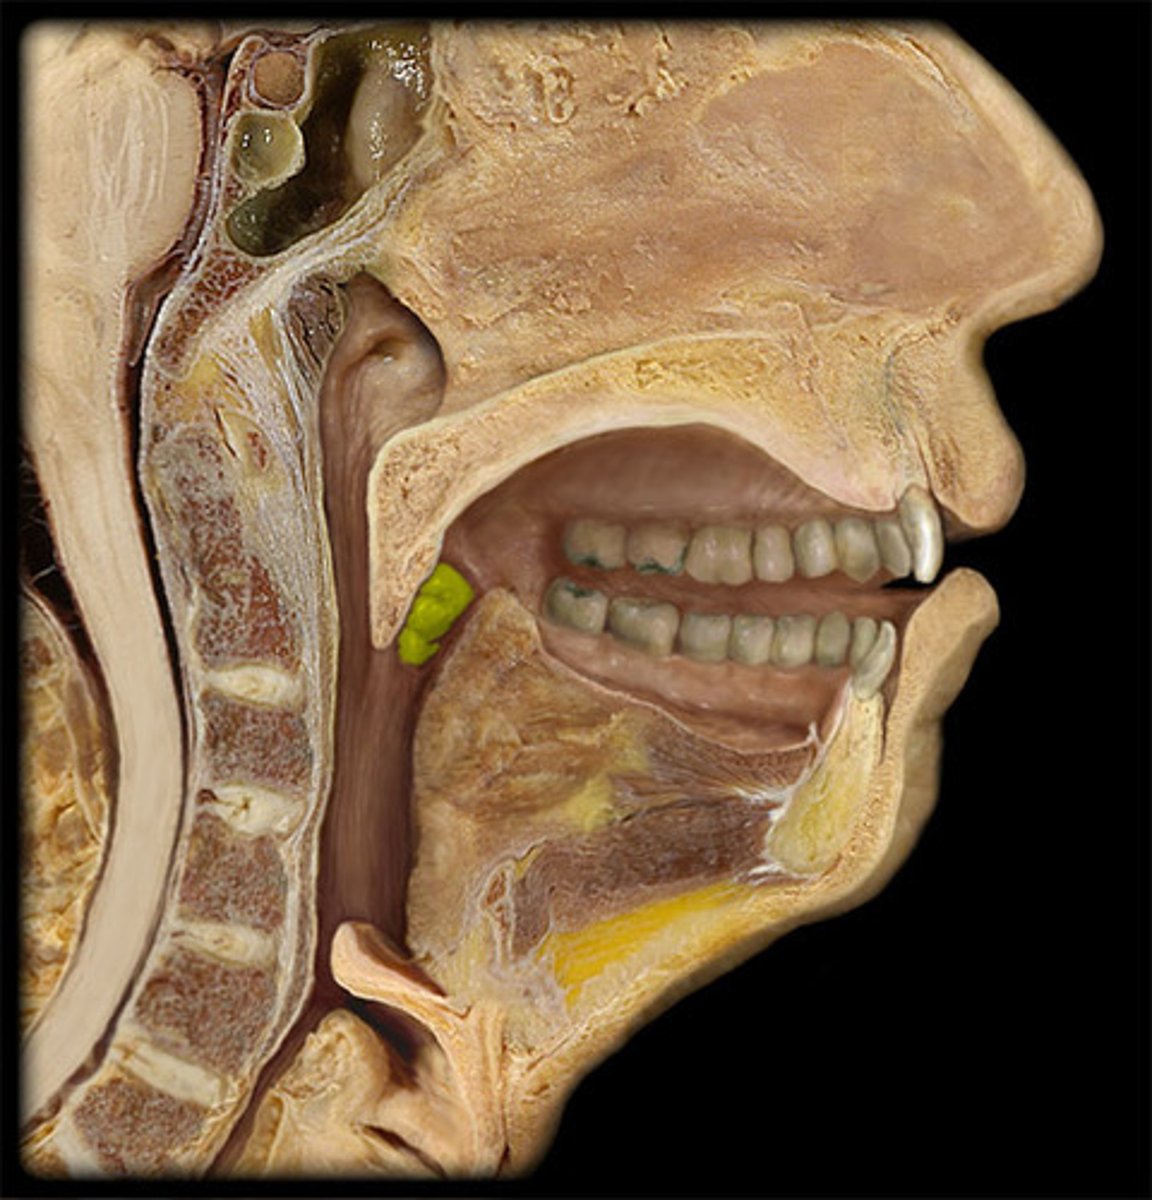

Parotid Salivary Gland

Submandibular Salivary Gland

Epiglottis

Thyroid Cartilage of Larynx

Cricoid Cartilage of Larynx

Thyroid Gland